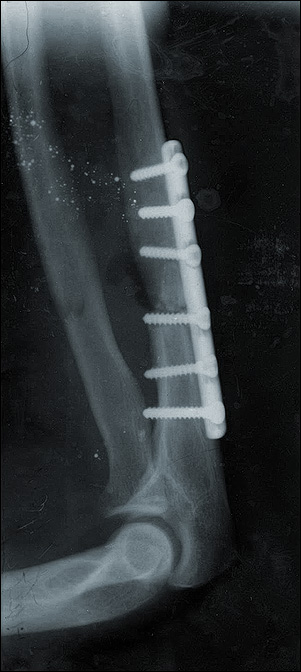

Здравствуйте. 16 февраля сломал локтевую кость руки. Закрытый перелом с отколовшимся кусочком. 21 февраля - операция - скрепление кости с помощью пластины и шести шурупов. Заживление прошло нормально, гипс снял на третьей неделе после операции. Потихоньку восстановилась подвижность, но остались некоторые болевые ощущения. Два вопроса: 1) Беспокоит что на рентгеновском снимке сделанном на 43 день после операции, картина ничем не отличается от снимка сразу после операции - та же светлая щель на месте совмещения перелома. Ясно видимы края перелома. Это нормально? 2) Шурупы выступают с другой стороны скреплённой ими кости. Это обычная практика? Беспокоит - не будут ли они каким-либо образом цеплять-повреждать мышечные ткани или лучевую кость? 3) Сегодня, через два месяца после операции, рука болит и отекает.Снимок изменений не показывает и не отличается от вышеприведённого.Что делать в моём случае, если врач делавший мне операцию, говорит только одно: "Не тревожить".Тупо терпеть или обратиться к другому специалисту?Может стоит принять участие в выздоровлении, ведь должны быть правильные методы наподобие электрофореза или чего-то подобного?Спасибо.

1)По снимку не видно, что есть какие-то большие проблемы. Для полноты картины лучше посмотреть на вторую проекцию. Отсутствие сращения месяца в 4-6 может уже быть основанием для каких-то активных действий.

2)выстояние винтов обычное, проблем не создает. 3)лечить надо не снимок, а пациента. То есть сейчас отломки фиксированы, надо восстановить амплитуду движений в локтевом и лучезапястном суставах, ротацию предплечья. "Правильные методы электофореза" существуют в той же мере, что и "ускорители беременности". Даже если не будет сращения через разумное время, что после накостного остеосинтеза случается Ё в 10-15% случаев из-за ухудшения кровообращения фрагментов при их обнажении, это не фатально. А вот вовремя не восстановленная функция суставов может оказаться потерянной безвозвратно.